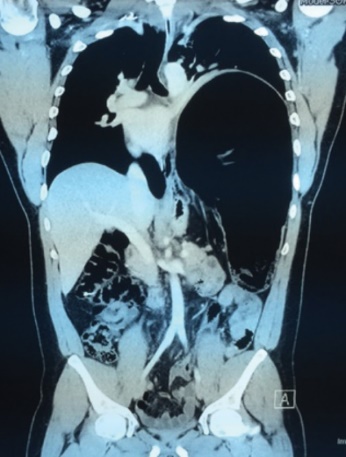

CT θώρακος-τραχήλου. Κόκκινα βέλη — Πολύ μεγάλη οπισθοστερνική βρογχοκήλη. Κίτρινα βέλη — Κλείδες (Ευγενική παραχώρηση Dr. V. Penopoulos)